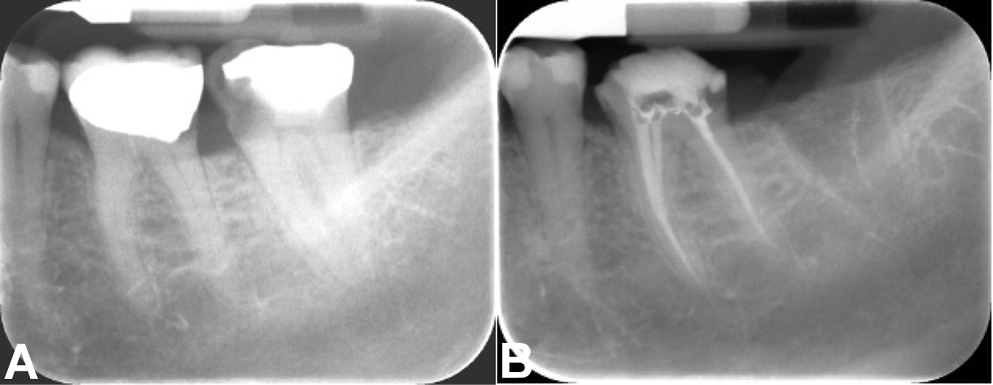

Group III: hot modified technique

The hot modified technique was performed following the protocol described in a previous report.44 After verification of the master cone, the premixed bioceramic sealer (Cerafill RCS®) was injected into the canal using a disposable tip. The master gutta-percha cone was lightly coated with the sealer and inserted to full working length.

A heated plugger set at 180°C was used for downpacking. The plugger was inserted to a depth of 6–10 mm short of the working length and activated for 4 s to thermosoften and compact the gutta-percha in the middle and coronal thirds. Care was taken to avoid disturbing the apical 3–4 mm to preserve the apical seal and prevent sealer extrusion.

The softened gutta-percha was vertically compacted using pre-fitted pluggers. Accessory cones were placed in wide canals to ensure adequate filling. Additional thermoplasticized gutta-percha was added as necessary to fill voids, and the quality of obturation was verified radiographically. Excess gutta-percha was removed to 1 mm below the canal orifice using a heated plugger and vertically compacted to complete the obturation (Figure 4).